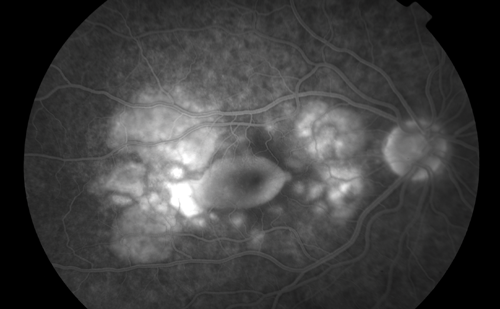

Figure 2: Fluorescein angiogram of the right posterior pole.

Fundus fluorescein angiography (FFA) (Figure 2) and indocyanine green angiography (ICG) showed evidence of choridal infiltrates, macular oedema and leaking retinal and choridal blood vessels.